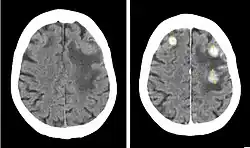

Contrast CT of a patient with brain metastases from breast cancer, before (left) and after (right) injection of iodinated contrast.

Iodinated contrast is a form of water-soluble, intravenous radiocontrast agent containing iodine, which enhances the visibility of vascular structures and organs during radiographic procedures. Some pathologies, such as cancer, have particularly improved visibility with iodinated contrast.